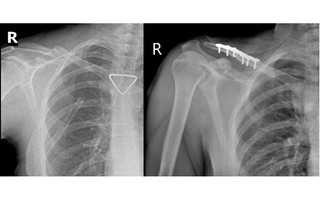

Thủng phổi sau khi hút cả bao thuốc lá mỗi ngày

(NLĐO) - Phổi bệnh nhân bị thủng, tràn khí vào màng phổi, không giãn nở được, gây khó thở sau thời gian dài hút thuốc lá